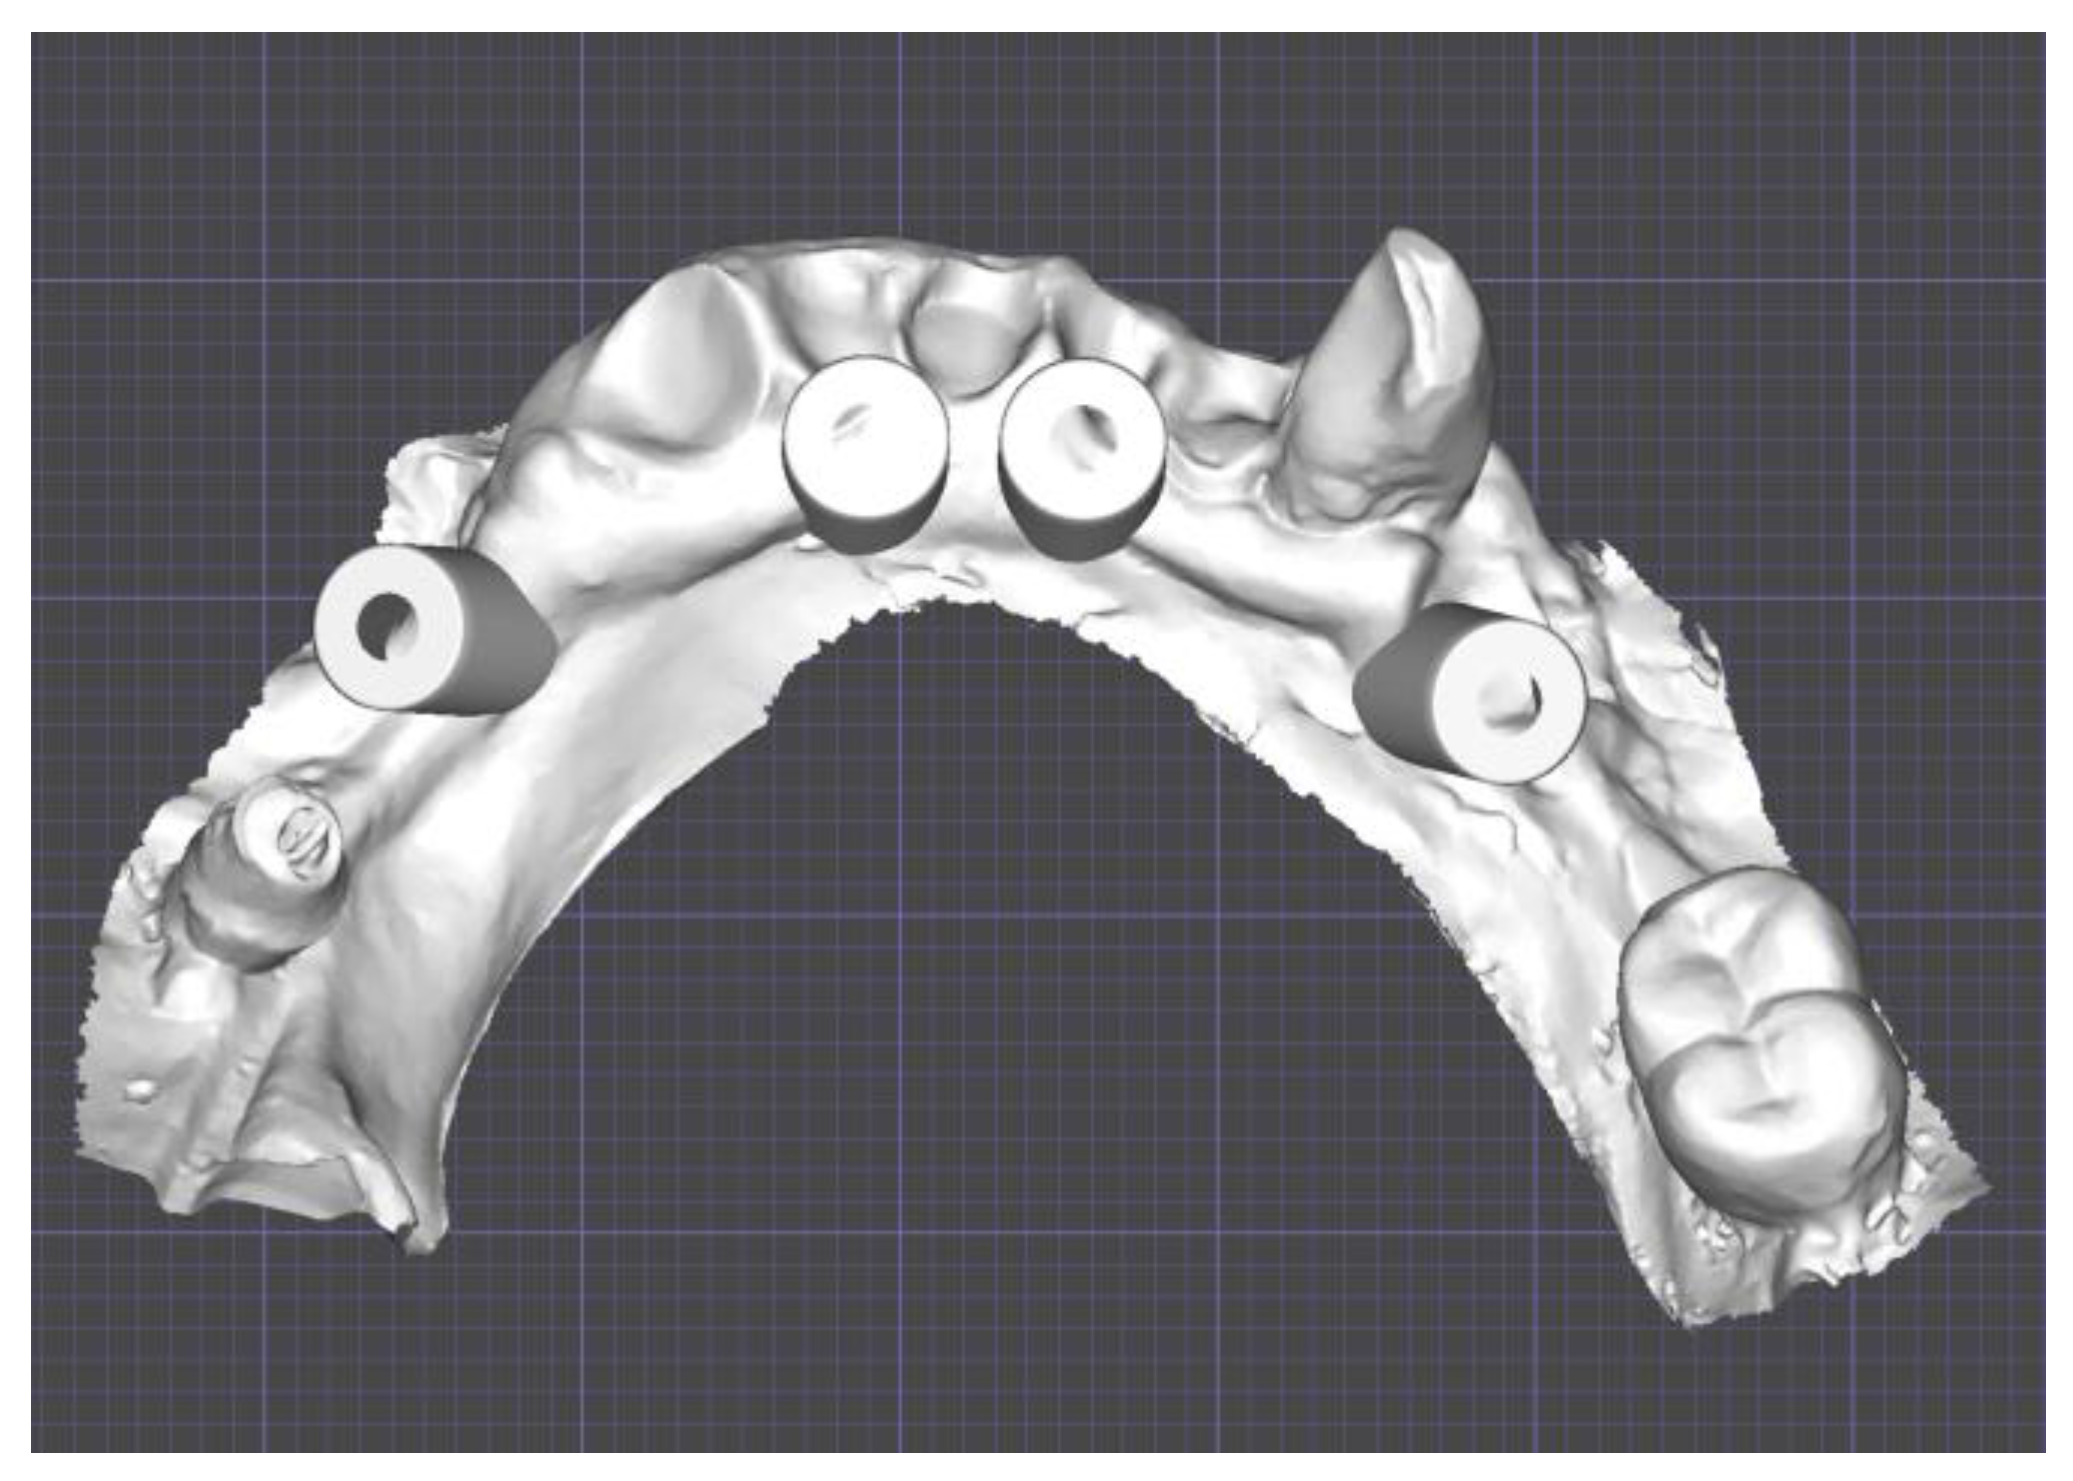

2.1. Planning

Surgical Guide

2.2. Provisional Prosthesis

2.3. Three-Dimensional Printing